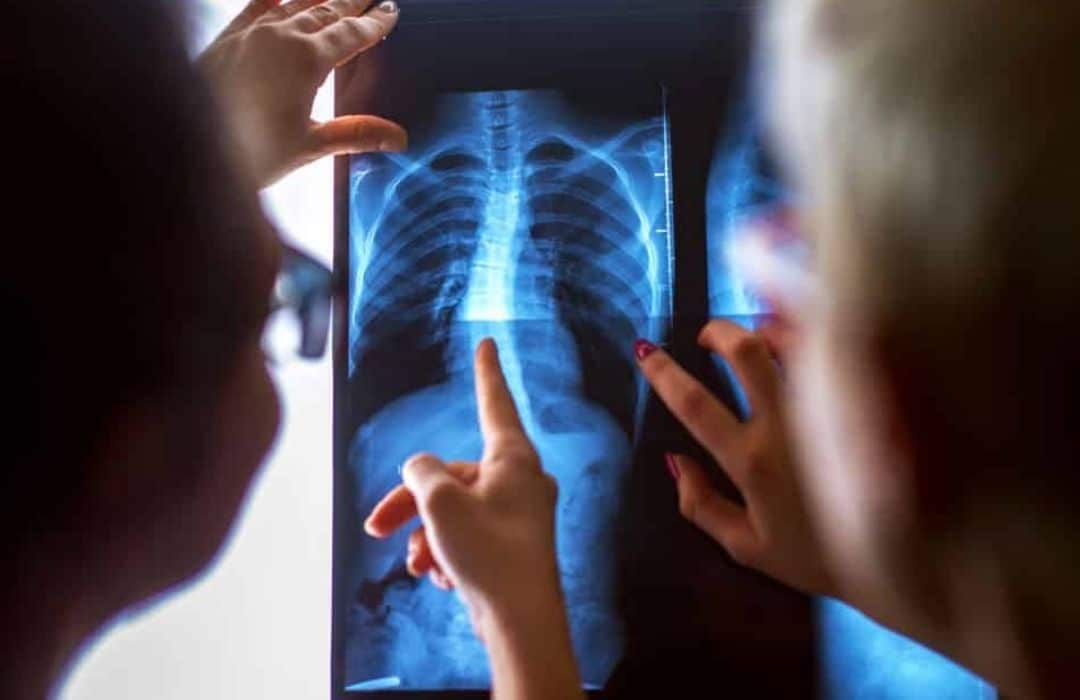

What about Lung Function?

Generally these patients will not have any lung function issues. However, having a Cobb angle of 50 degrees or more at skeletal maturity is a significant predictor of reduced pulmonary function (1). Patients with very large major curves of more than 80 degrees with a thoracic apex have more chances of having shortness or breath compared to patients with major lumbar curves of 50 degrees or more (1).